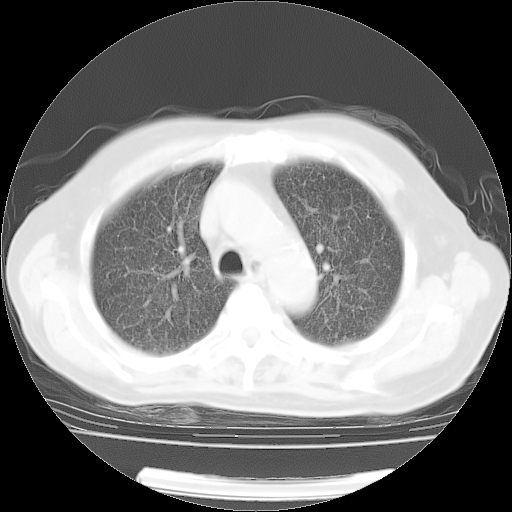

4月14日肺部CT